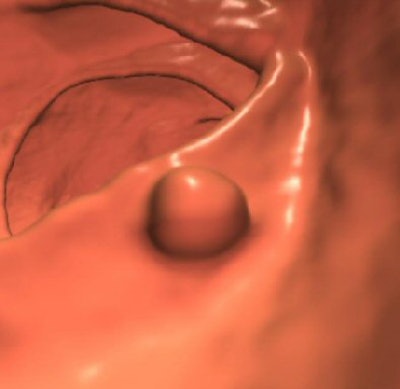

| Top, colon map from screening CTC shows the location of three polyps that measured 6-9 mm in size (C-RADS 3 classification). Below, 3D endoluminal CTC image shows a 6-mm polyp in the ascending colon. Bottom, image from same-day optical colonoscopy shows the same polyp, which proved to be a tubular adenoma. The other two polyps (8 and 9 mm in size) also proved to be tubular adenomas. All images courtesy of Dr. Perry Pickhardt. |